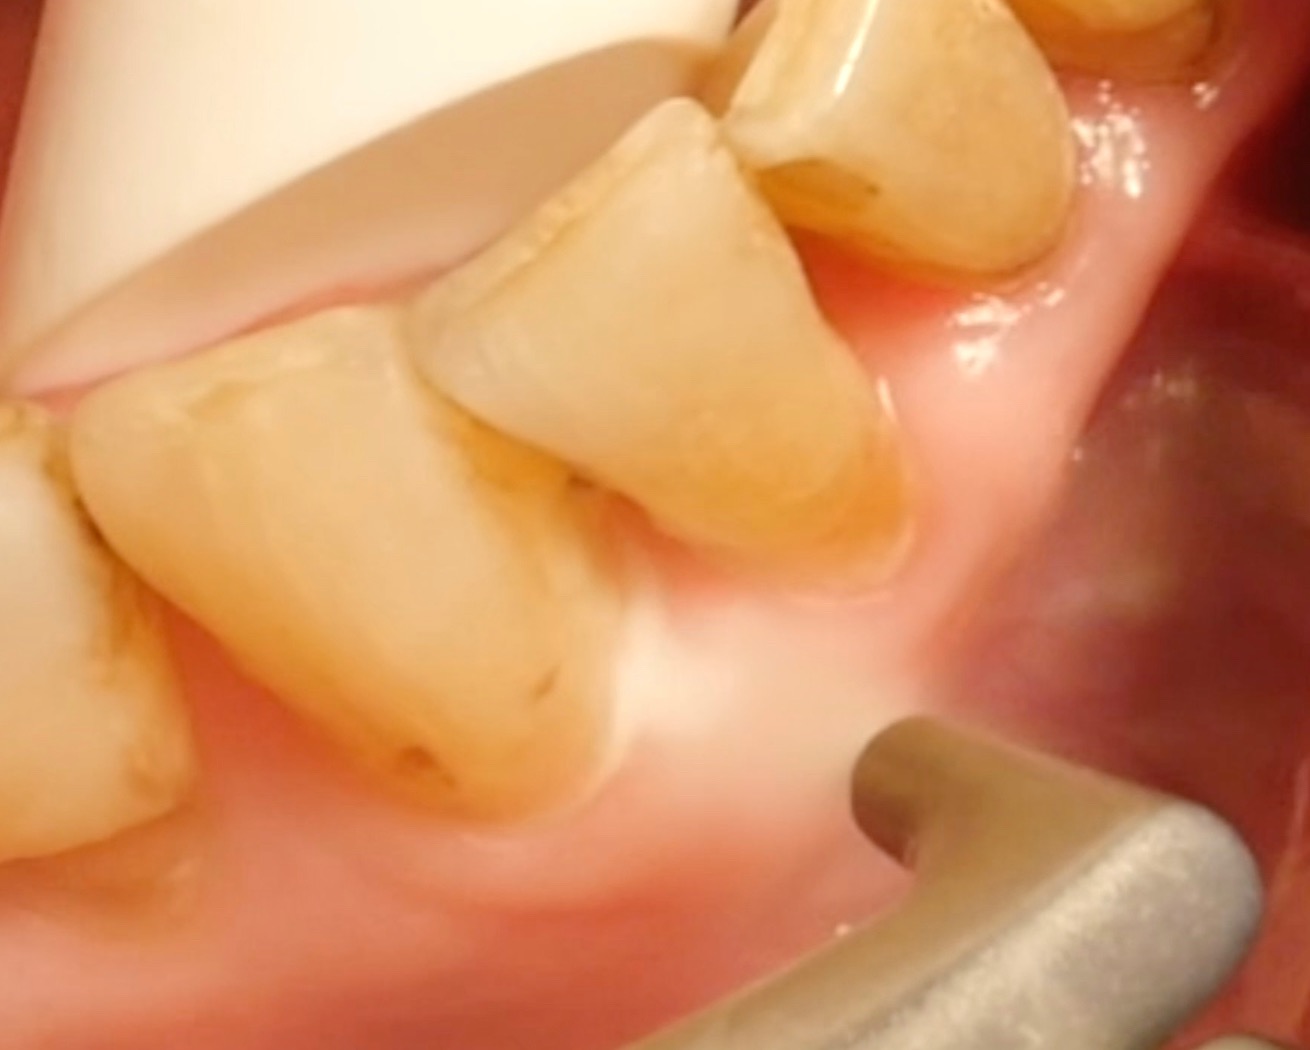

• However, it is essential to note that air-polishing devices cannot ablate deposits of tartar and calculus; here, a combination of (ultra)sonic devices and/or hand instruments must be used.